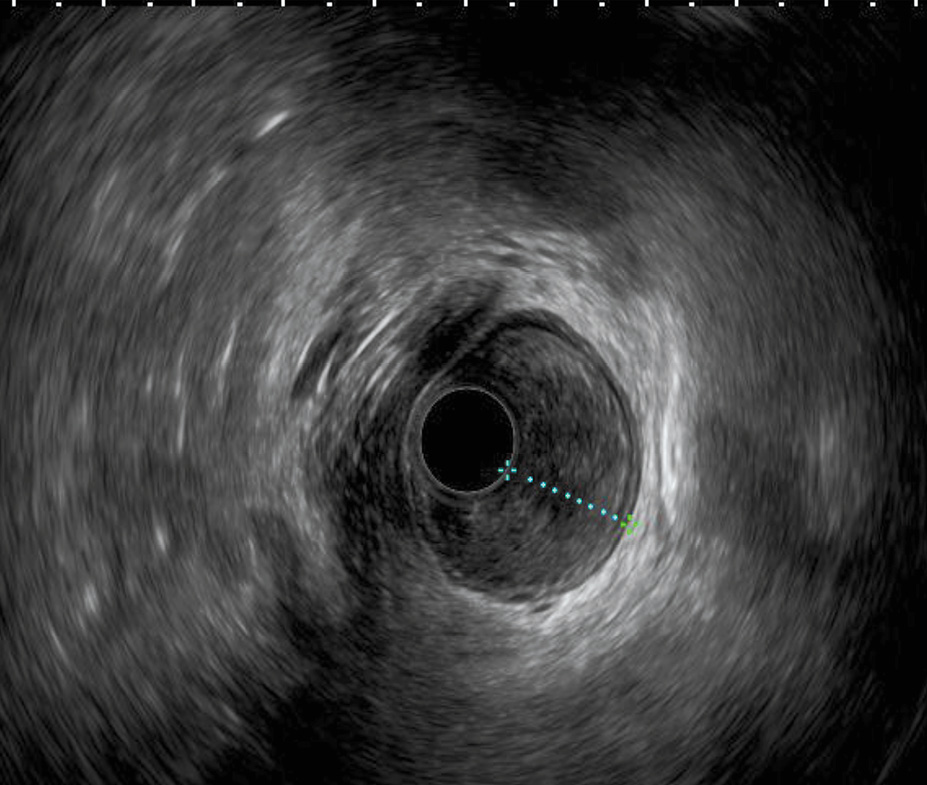

Вторая подгруппа включала 30 больных с распространением рака тела и проксимального отдела желудка на абдоминальный сегмент пищевода. Всем им также были проведены ЭГДС и ЭндоУЗИ. При сопоставлении результатов ЭГДС и ЭндоУЗИ у 25 (76,7%) человек проксимальная граница опухоли совпадала, а у 7 (23,3%) отличалась. Различие данных относительно проксимальной границы опухоли подтверждает большую площадь распространения опухолевого процесса по результатам ЭндоУЗИ и составляет до 1 см. Различие между результатами ЭГДС и ЭндоУЗИ может быть обусловлено подслизистым характером роста опухоли (рис. 3, 4).

Рис. 4. Эндосонографическая картина опухоли проксимального отдела желудка с распространением на абдоминальный сегмент пищевода. На фото: сканирование из просвета пищевода. Инвазия опухоли на все слои стенки пищевода. / Fig. 4. Endosonographic image of a proximal gastric tumor with involvement of the abdominal segment of the esophagus. Pictured: a scan from the esophageal lumen. Tumor invasion into all layers of the esophageal wall.